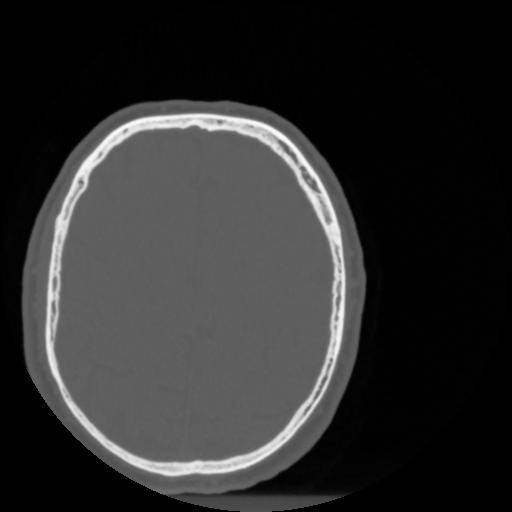

4 CEREBRO,,Vol,0.5,CEREBRO,,